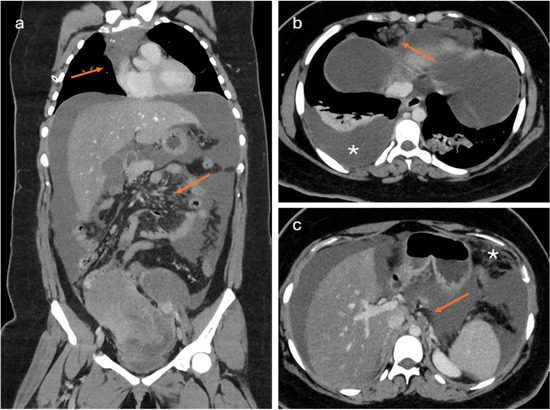

The Role of Computed Tomography-Determined Total Tumor Volume at Baseline in Predicting Outcomes of Patients with Locally Advanced Unresectable or Metastatic Pancreatic Ductal Adenocarcinoma

Background: Total tumor volume (TTV), derived from imaging data, has emerged as a potential prognostic biomarker in various cancers. This study aimed to evaluate the impact of TTV on outcomes in advanced pancreatic ductal adenocarcinoma (PDAC) and to validate a survival prediction model combining TTV with baseline clinico-biological markers. Materials and Methods: We conducted a retrospective analysis of 150 patients with locally advanced or metastatic PDAC treated with first-line FOLFIRINOX from 2010 to 2021. TTV was calculated by manually segmenting all visible lesions on baseline CT scans. Progression-free survival (PFS) and overall survival (OS) were the primary endpoints. A cut-off value for TTV predicting 6-month PFS was determined in 140 patients using AUC and Youden’s Index and then applied to OS analysis. A multivariate Cox regression model incorporating TTV, CA 19-9, and neutrophil-to-lymphocyte ratio (NLR) was developed in 94 patients to establish a survival risk score. Results: 12,028 lesions were annotated. OS was slightly but significantly different between TTV above and below the median value of 69.60 cm3 (12.4 vs. 13.5 months, p = 0.0269). A cut-off of 400 cm3 distinguished two groups: patients with TTV > 400 cm3 had significantly shorter OS (9.4 months) compared to those with TTV ≤ 400 cm3 (13.0 months, p = 0.0056). A similar trend was observed for PFS, though not statistically significant (7.4 months for TTV > 400 cm3 vs. 8.2 months for TTV ≤ 400 cm3, p = 0.0735). The combined model achieved a mean c-index of 0.62 for PFS and 0.64 for OS. Based on the risk score, high-risk patients had significantly worse median PFS (5.5 vs. 9.2 months, p = 0.0008) and median OS (7.2 vs. 13.5 months, p < 0.0001). Conclusions: TTV is a valuable prognostic marker in advanced PDAC. A model integrating TTV with biological markers enhances survival prediction and supports risk stratification in clinical practice.